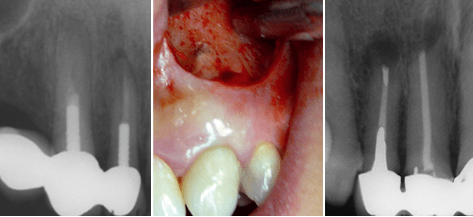

Gerade bei der Beurteilung von etwaigen Haftungsansprüchen bei zivilrechtlichen Auseinandersetzungen sind Leitlinien bzw. wissenschaftliche Stellungnahmen der medizinischen Fachgesellschaften zunehmend ins juristische Interesse gerückt. Da bekannt ist, dass Leitlinien häufiger von Juristen als von Ärzten eingesehen werden, sollten im Falle eines Zivilstreites diese durch den Sachverständigen im zahnärztlichen Gerichtsgutachten Berücksichtigung finden (Brauer et al. 2008). Daher ist auch die Kenntnis der wissenschaftlichen Stellungnahme der Deutschen Gesellschaft für Zahn-, Mund- und Kieferheilkunde (DGZMK) zur Revision einer Wurzelkanalbehandlung unabdingbar, die den Verzicht auf eine orthograde Revision und die Entscheidung für einen rein apikal-chirurgischen Eingriff nur dann als sinnvoll erachtet, wenn auf orthogradem Wege ein ausreichender Zugang in das endodontische System oder eine Verbesserung des Zustandes auf orthogradem Wege nicht möglich/wahrscheinlich erscheint (Hülsmann und Weiger 2004) (Abb. 1).

Abb.1: Indikation zur retrograden WSR an 13 und 12.- Abb.2: Exploration des Periapex an 23 mit klassischem Bogenschnitt nach Partsch.- Abb.3: Post-operativer Zahnfilm. Retrograde WSR an 12 und orthograde WSR an 11.